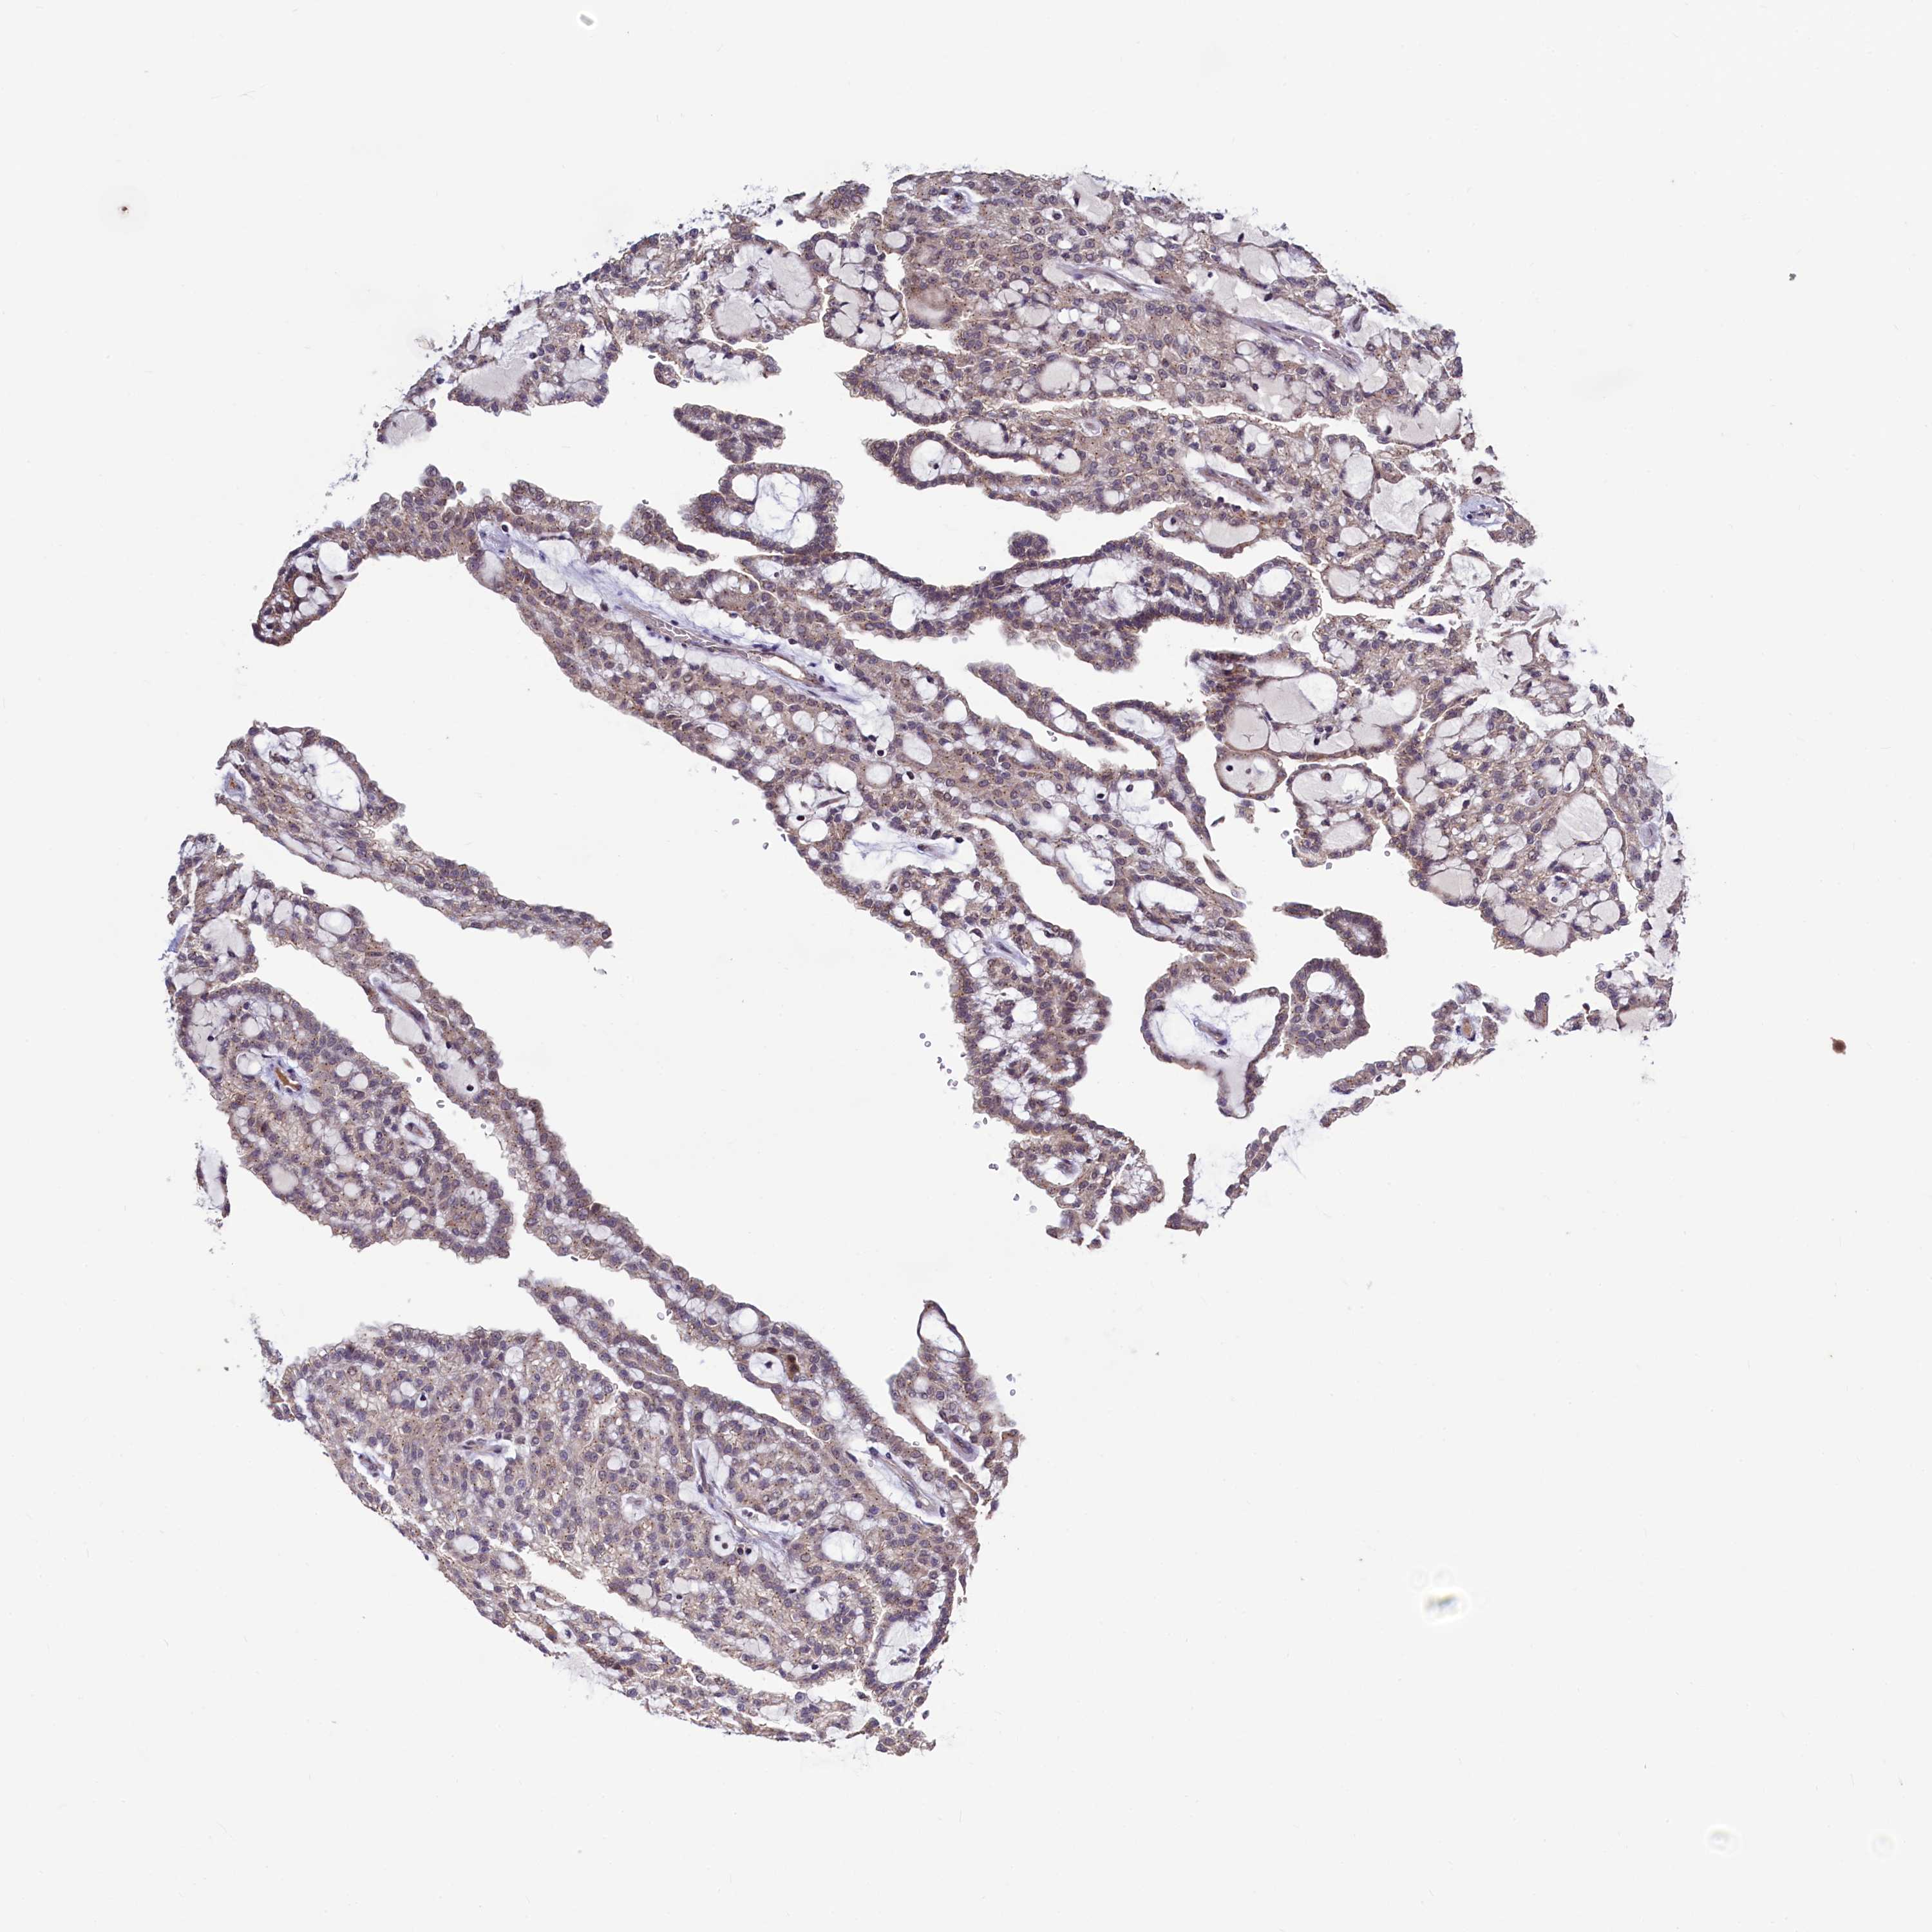

KIDNEY RENAL CLEAR CELL CARCINOMA (VALIDATION) - Interactive survival scatter ploti

The Survival Scatter plot shows the clinical status (i.e. dead or alive) for all individuals in the patient cohort, based on the same data that underlies the corresponding Kaplan-Meier plots. Patients that are alive at last time for follow-up are shown in blue and patients who have died during the study are shown in red.

The x-axis shows the expression levels (FPKM) of the investigated gene in the tumor tissue at the time of diagnosis. The y-axis shows the follow-up time after diagnosis (years). Both axes are complimented with kernel density curves demonstrating the data density over the axes. The top density plot shows the expression levels (FPKM) distribution among dead (red) and alive patients (blue). The right density plot shows the data density of the survived years of dead patients with high and low expression levels respectively, stratified using the cutoff indicated by the vertical dashed line through the Survival Scatter plot. This cutoff is automatically defined based on the FPKM cutoff that minimizes the p-score. The cutoff can be changed by dragging the vertical line or by entering a cutoff value in the square labeled "Current cut-off".

Under the Survival Scatter plot the p-score landscape (black curve; left axis) is shown together with dead median separation (red curve; right axis). Dead median separation is the difference in median mRNA expression between patients who have died with high and low expression, respectively. It is calculated as follows: median FPKM expression of dead patients with high expression - median FPKM expression of dead patients with low expression. This is intended to aid the user in visually exploring custom cutoffs and the associated p-scores and dead median separation.

Individual patient data is displayed and can be filtered by clicking on one or more of the category buttons on the top of the page. Categories describing expression level and patient information include: high, low, alive, dead, female, male and tumor stages. The scale of the x-axis can be toggled between linear and log-scale by clicking on the "x log" button. Mouse-over function shows TCGA ID, patient information and mRNA expression (FPKM) for each patient.

& Survival analysisi

Kaplan-Meier plots summarize results from analysis of correlation between mRNA expression level and patient survival. Patients were divided based on level of expression into one of the two groups "low" (under cut off) or "high" (over cut off). X-axis shows time for survival (years) and y-axis shows the probability of survival, where 1.0 corresponds to 100 percent.

SEC24C is not prognostic in Kidney Renal Clear Cell Carcinoma (validation)

: 44.65

Average pTPM 42.4

Number of samples 100